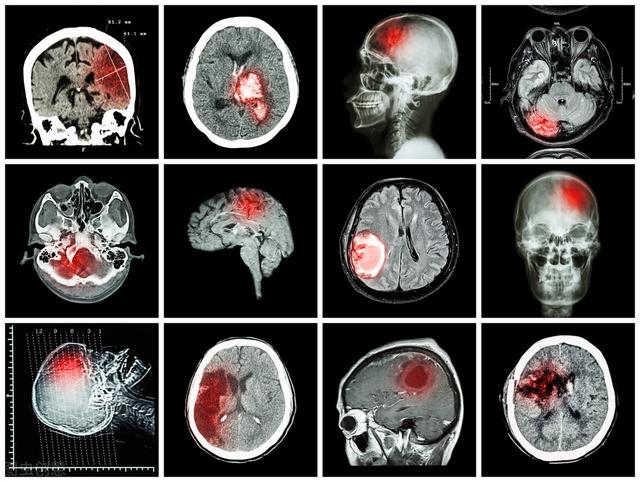

脳梗塞発症後24〜48時間後に脳のCT検査を行うと、対応する部位に境界のはっきりしない低密度の病巣が認められ、何らかの占拠作用がある可能性がある。脳磁気共鳴(MRI)検査では、病変部のT1低信号と加重画像のT2高信号によって示される脳梗塞を早期に発見することができ、MRIはより小さな梗塞病変を検出することができる。

海綿状脳梗塞は、一般的な脳血管障害の一つであり、持続性高血圧と小動脈硬化に起因する特殊な脳血管障害で、直径100〜400μmの深部貫通枝の閉塞による微小梗塞である。末期には、軟化した微小病巣から壊死組織が除去され、小さな嚢胞状の空洞が残るため、海綿状脳梗塞と呼ばれる。